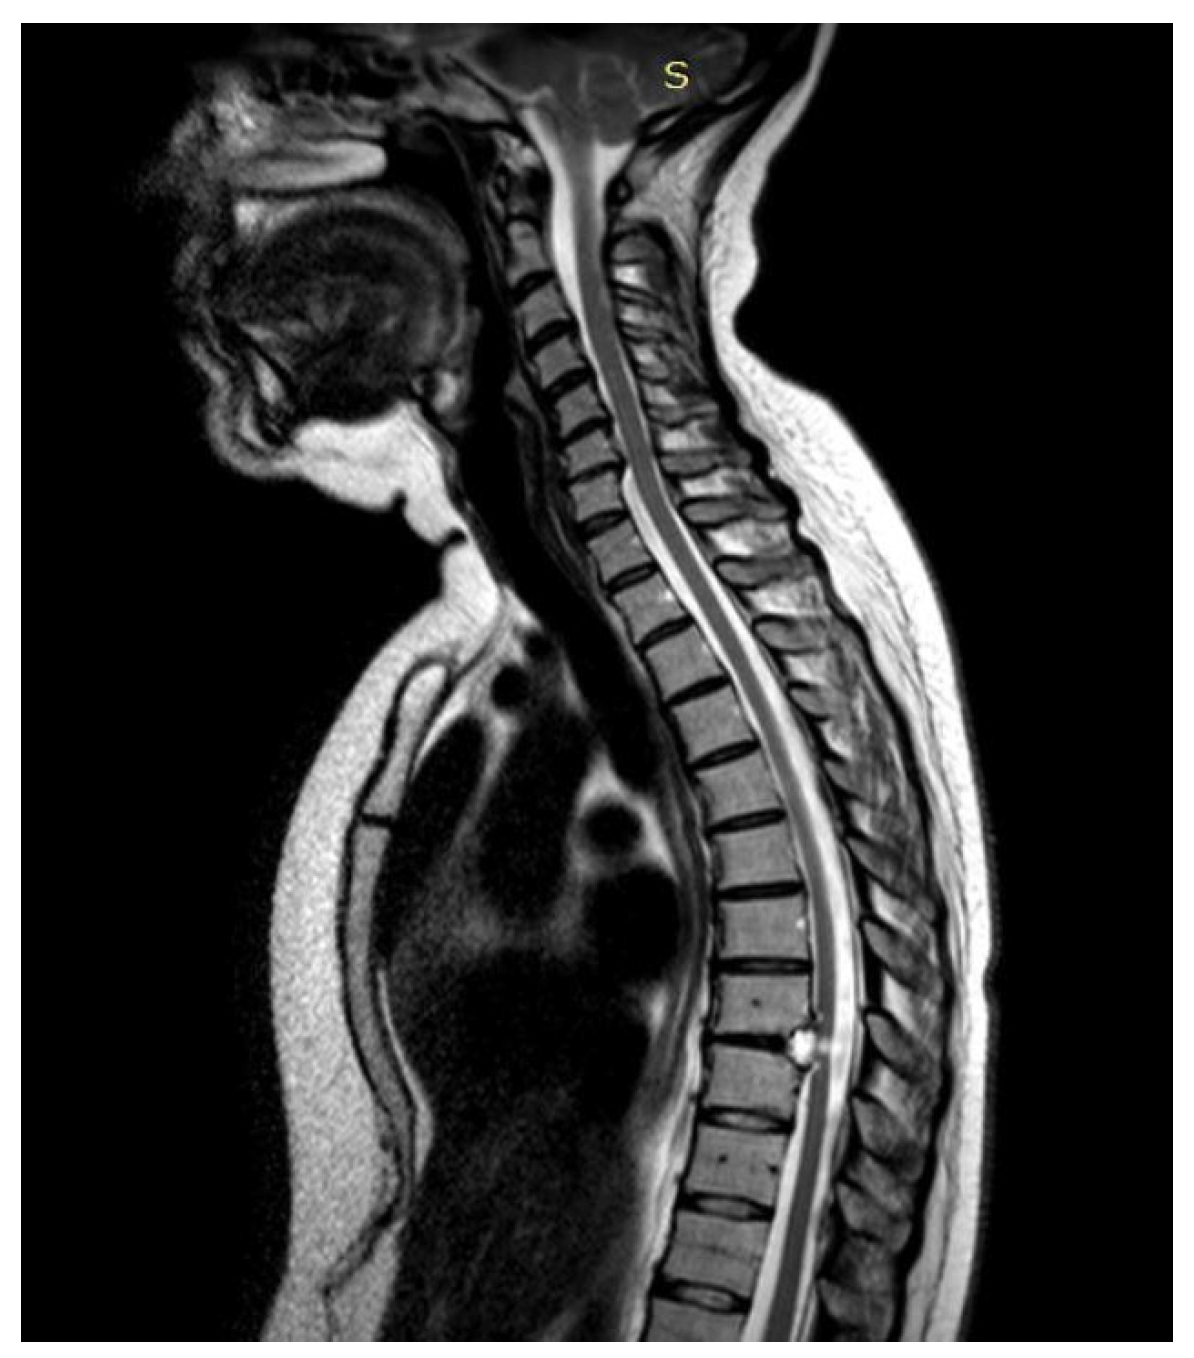

3.4.1. Case 1

| Level | T12–L2 | C5–C6 | T7–T10 | T8–T9 | T8–T11 |

| Location | Intramedullary | Intradural | Intradural–Extradural | Intramedullary | Intradural |

| Surgical treatment | lysis of adherences and syrinx cavity opening | resection of the cystic formation and adhesiolysis | resection of the cystic formation and adhesiolysis | resection of the cystic formation and adhesiolysis | resection of the cystic formation and adhesiolysis |